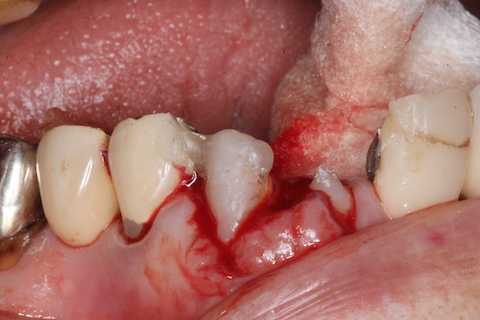

前回 ​のつづきで、再植と化粧をする。さすがに歯なしでは寂しい。

普通にズブズブと抜歯窩に再建した歯根を挿入する。